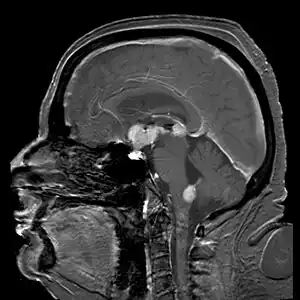

Brain magnetic resonance imaging showing primary central nervous system B-cell non-Hodgkin lymphoma of the sella turcica and hypothalamus, continuing to the tectum (intensely white areas in the middle).

MRI or contrast enhanced CT classically shows multiple ring-enhancing lesions in the deep white matter. The major differential diagnosis (based on imaging) is cerebral toxoplasmosis, which is also prevalent in AIDS patients and also presents with a ring-enhanced lesion, although toxoplasmosis generally presents with more lesions and the contrast enhancement is typically more pronounced. Imaging techniques cannot distinguish the two conditions with certainty, and cannot exclude other diagnoses. Thus, patients undergo a brain biopsy or vitreous biopsy, if there is intraocular involvement.[10]